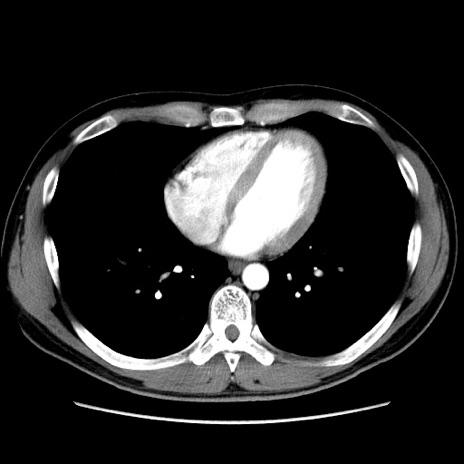

症例36(横断像)

【症例】20歳代 男性

【主訴】心窩部痛

【現病歴】今朝より上腹部痛あり。一旦軽快していたが再度出現したため救急要請。昨日夕に白身の魚を含む刺身を食べた。

【身体所見】BP 136/89mmHg、HR 74/min、BT 37.0℃、腹部:膨満、軟、心窩部に圧痛あり。反跳痛なし、筋性防御なし、腸雑音やや亢進あり。

【データ】WBC 17700、CRP 0.48